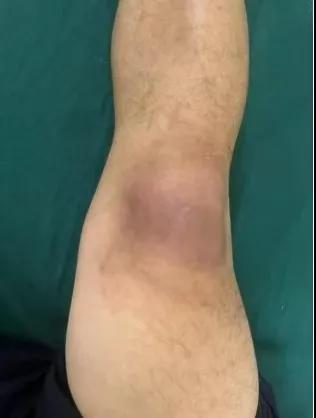

近日,漯河醫(yī)專二附院(漯河市骨科醫(yī)院、漯河市立醫(yī)院)手顯微外科(骨四科)李俊明主任團隊應用清熱解毒、拔毒生肌類中藥(骨炎膏)外用結合抗生素成功治愈一例膝關節(jié)外傷后軟組織感染病人。

患者,以“外傷致右膝紅腫、疼痛20余天”為主訴就診,20余天前,因騎電車摔傷右膝關節(jié),致使出現右膝腫脹、疼痛、活動受限,在當地醫(yī)院給予消腫、止痛治療效果差,繼而出現膝關節(jié)紅腫熱痛癥狀,門診給予滑膜炎片及消腫止痛藥物治療癥狀未見好轉,慕名前來我院手顯微外科住院。入院當天即給予中藥外敷(骨炎膏),穿刺膿性分泌物送細菌培養(yǎng),給予廣譜抗生素治療(細菌培養(yǎng)未出)。

中藥外敷(骨炎膏)主要適用于局部紅腫熱痛,四肢血栓形成、靜脈炎等,具有清熱解毒,拔毒生肌的作用。

中藥外敷骨炎膏給藥直接作用于病灶,彌補了單純口服藥物局部濃度不足的缺陷;同時,中藥外敷與抗生素的系統(tǒng)性抗感染形成"靶向-全身"雙重干預,可顯著縮短療程并降低耐藥風險,更為中西醫(yī)結合治療軟組織感染提供新的思路。(盧 闖 賈煒煒 劉 旭 袁錦鈺)